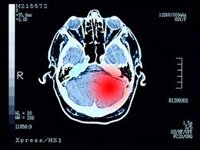

Investigadores del CIBER en sus áreas de Cáncer (CIBERONC), enfermedades respiratorias (CIBERES) y enfermedades cardiovasculares (CIBERCV) han colaborado en la caracterización de las lesiones pulmonares, cardíacas, hematopoyéticas y del sistema nervioso central en pacientes fallecidos por COVID-19.

El estudio detallado de las autopsias ha demostrado que un número significativo de pacientes desarrollan proliferaciones vasculares pulmonares anormales, que pueden participar en el desarrollo del nivel de oxigeno inferior de lo normal o hipoxemia severa. Asímismo, se ha demostrado la presencia de virus en tejido pulmonar con capacidad replicativa en pacientes con inmunodeficiencia severa hasta después de 100 días de evolución de la enfermedad.

Casi todos los pacientes desarrollaron linfohistiocitosis hemofagocítica secundaria, síndrome caracterizado por la desregulación de la respuesta inmune y cierto grado de neuroinflamación cerebral, probablemente secundarias a las respuesta inmune frente al virus. Igualmente, las lesiones directas del virus sobre el corazón fueron infrecuentes, observándose lesiones de miocarditis en menos del 5% de los casos.

Estos estudios autópsicos ayudan a entender mejor la evolución clínica de los pacientes con COVID-19 letal, así como las posibles secuelas en pacientes que se recuperan tras una enfermedad grave.